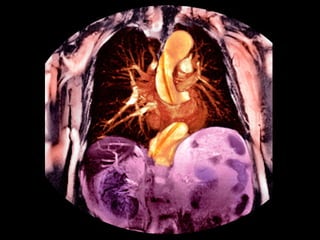

Die akute Aortendissektion

Diagnose und Management in der Prähospitalphase

„Die akute Aortendissektion ist aufgrund der hohen

Frühmortalität eine bedrohliche Notfallsituation.

Notärzte müssen typische Indizien kennen und zielgerichtet

überprüfen.“

Einteilung

DeBakey I    DeBakey II    DeBakey III

Stanford A   Stanford A    Stanford B

Die akute Aortendissektion Diagnose und Management in der Prähospitalphase „Die akute Aortendissektion ist aufgrund der hohen Frühmortalität eine bedrohliche Notfallsituation. Notärzte müssen typische Indizien kennen und zielgerichtet überprüfen.“

Die akute Aortendissektion Einteilung DeBakey I DeBakey II DeBakey III Stanford A Stanford A Stanford B